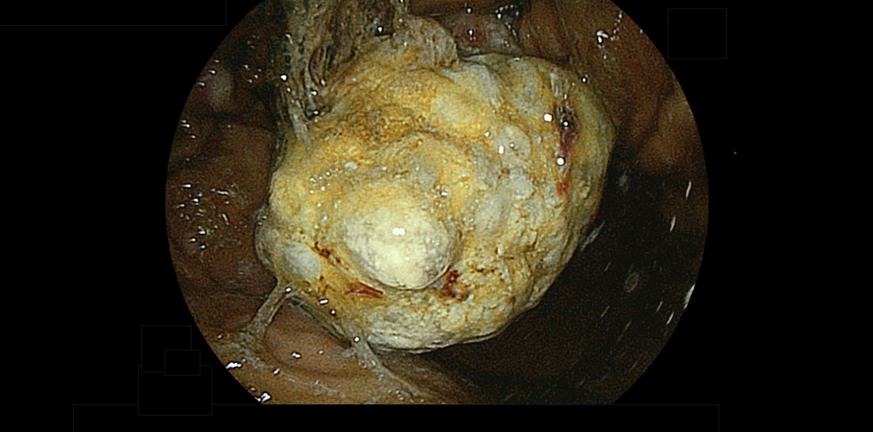

食道がんは飲酒や喫煙が主な危険因子であり、熱い食べ物、塩分の多い食べ物もリスクと考えられています。40歳代以降の男性に多く、早期では無症状ですが、進行すると食べ物を飲み込むときに胸がしみる感じ、つかえる感じ、胸痛が生じます。早期に発見できれば内視鏡治療を含む低侵襲な治療が選択可能となります。飲酒や喫煙をされる方や熱い食べ物、塩分の多い食べ物を好む方、バレット食道の診断がついた場合、定期的に内視鏡検査で経過観察を行うことをお勧めします。

欧米と比較し日本で多い傾向にあり、日本人のがんによる死亡原因の第2位です。一般的な胃がんは胃炎や萎縮を起こしている粘膜から発生すると考えられています。原因はピロリ菌感染が多くを占めますが、喫煙や塩分の過剰摂取、栄養バランスの偏った食事なども要因と考えられています。早期の胃がんや特殊なタイプの胃がんを発見するための内視鏡的な診断する技術や、発見したがんを治療する技術が進歩しており、がんの早期発見と治療が可能になっています。定期的に内視鏡検査を行うことで早期発見と早期治療を可能にします。

平均寿命の高齢化に加え、食生活の欧米化など様々な要因もあり、大腸がんの患者数や死亡者数は増加傾向にあります。大腸がんは初期では症状を自覚することが少なく、気付かないうちに進行します。症状が出てから診断に至った場合には、内視鏡治療などの低侵襲な治療が選択出来ないことがあります。大腸ポリープ切除術を行うことで、大腸がんによる死亡を予防できることも報告されています。繰り返す下痢や便秘などの排便異常や血便、便潜血反応陽性の方は大腸内視鏡検査をお勧めします。